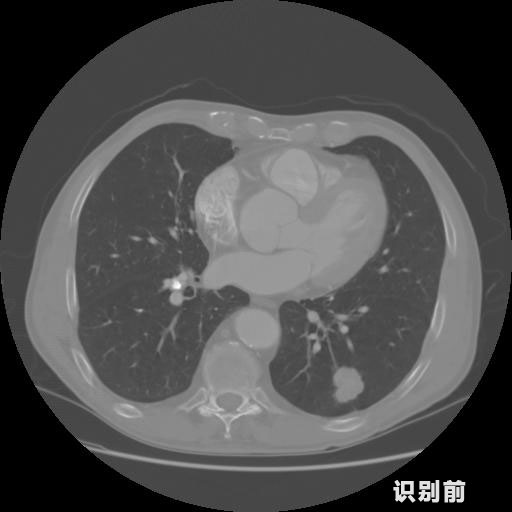

英特健康A(chǔ)I深度學(xué)習(xí)醫(yī)療圖像識別系統(tǒng)案例_胸部CT

1.發(fā)現(xiàn)肺結(jié)節(jié)的可能性為95.56%---位于框指數(shù)位置:[331.70554 366.13406 365.21707 403.96234]